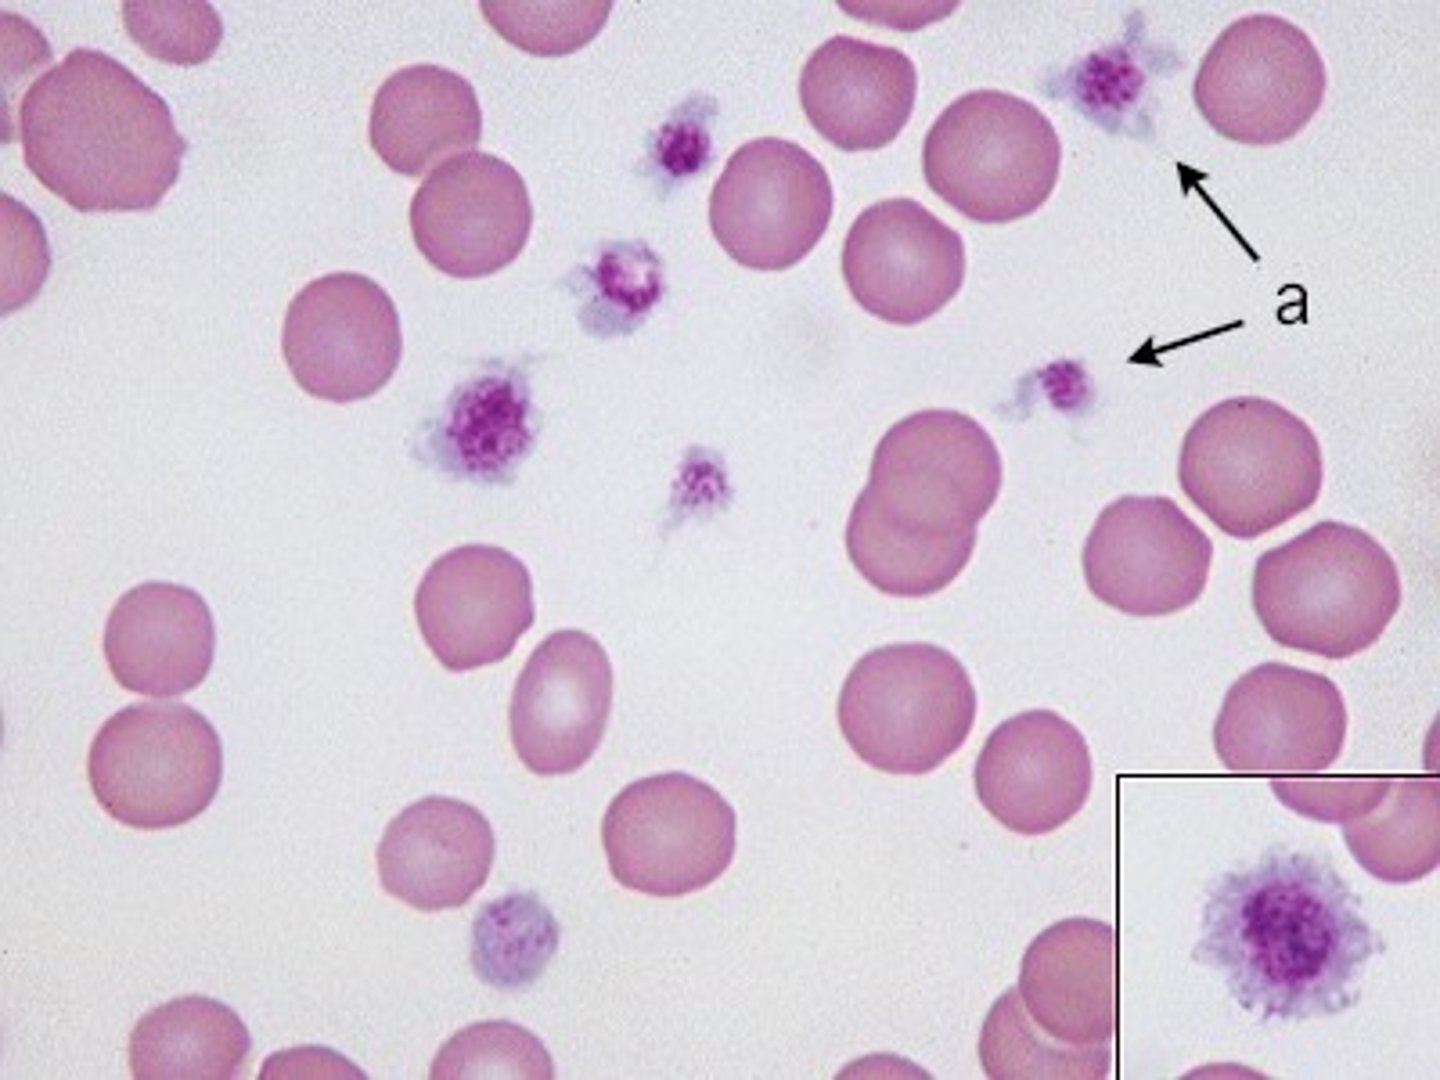

Blood

What is this?

Abnormal

Is this blood slide normal or abnormal?

platelet

what is this?

Red Blood Cell

what is this?